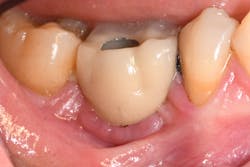

If the occlusal forces delivered to the implant-abutment-crown complex exceed the screw’s clamping ability, this may result in either its loosening (figures 1a and 1b) or, in more severe situations, fracturing of the screw (figures 2a–2c). Clinicians often indite the occlusion as being the primary culprit for the problem; however, in a number of instances, this may not be the case. The cause of screw loosening could also be due to using aftermarket parts, which do not have the precise fit of those made by the manufacturer of the implant.7